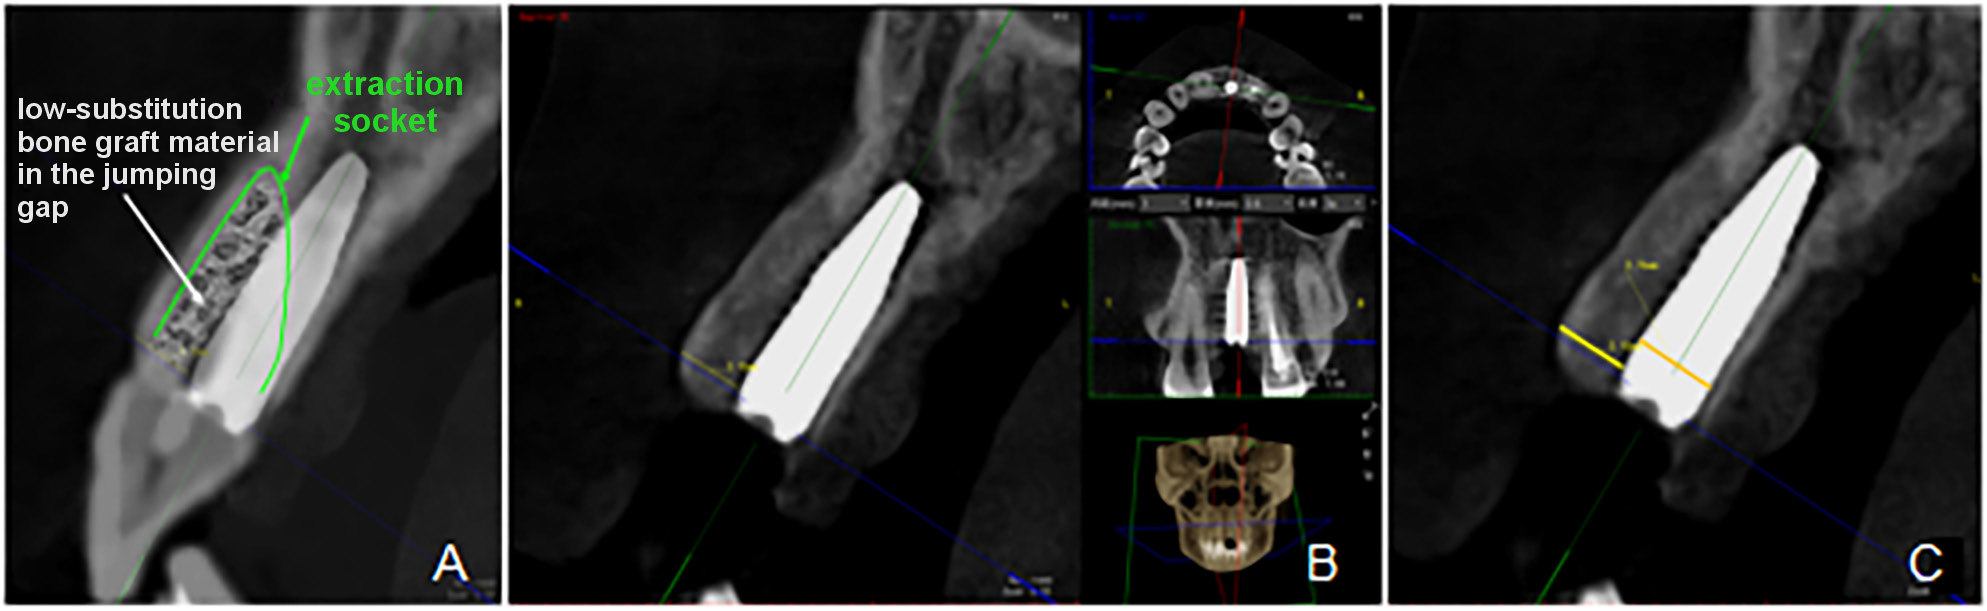

The SmartVPro software, v. 2.1.1.4895 (LargeV, Beijing, China), equipped with a proprietary linear measurement tool, was used to measure the labial alveolar bone thickness and the implant diameter in the multiplanar reconstruction (MPR) CBCT scans obtained immediately postoperatively. The focal planes of the CBCT scans were adjusted to the center of the implant in both the mesiodistal and buccolingual dimensions,20 with the oblique sagittal view oriented perpendicular to the dental arch.

In the CBCT images, the labial alveolar bone thickness – comprising the labial socket wall and the jumping gap filled with Bio-Oss Collagen – was measured at the cervical level of the implant, as illustrated in Figure 3. All measurements were independently performed by 2 trained assessors to minimize the observer bias.